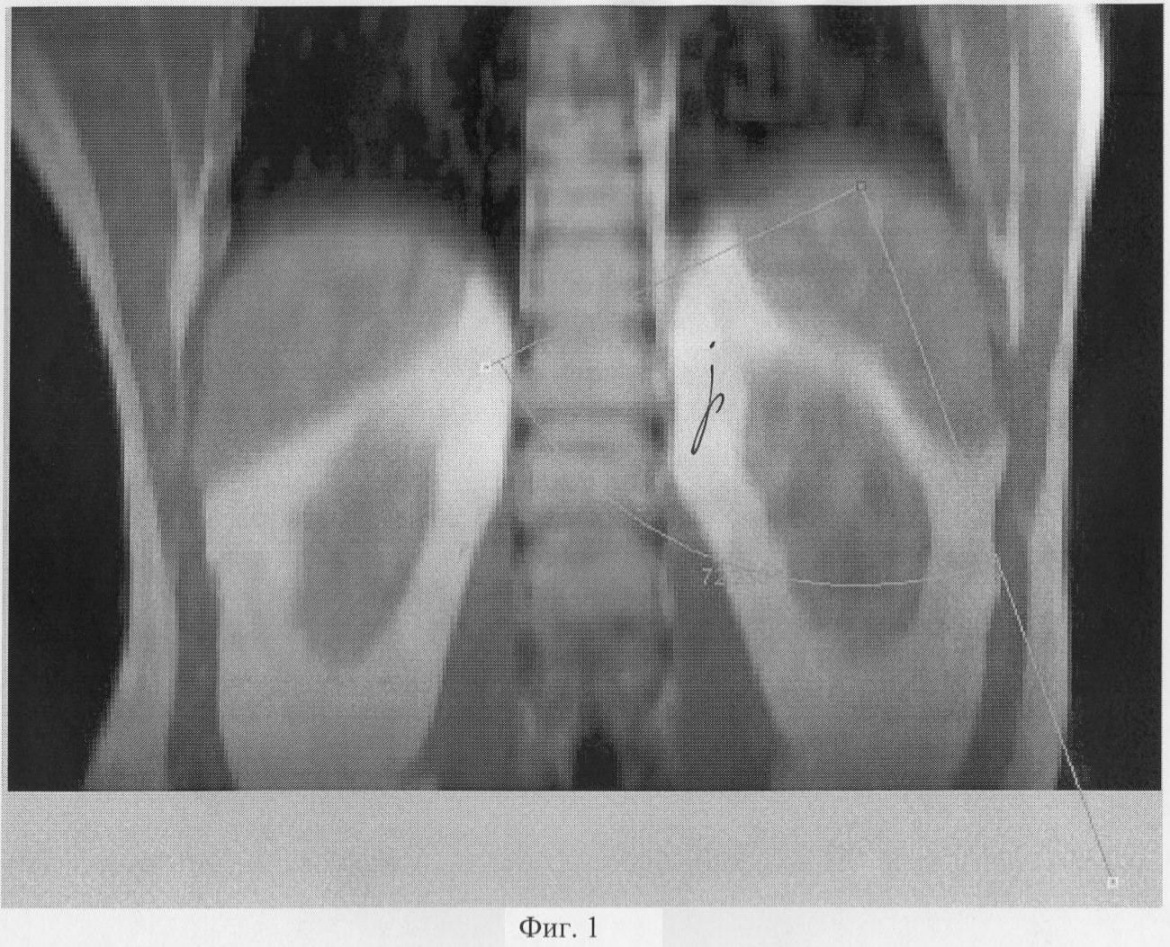

На Фиг.1 показан угол в прямой проекции с ориентацией на сосудистый пучок селезенки.

Измерялись углы между оптической осью эндоскопа (ось операционного действия) и манипуляционными портами и УОД – углы , , , при этом вершина угла ориентировалась на сосудистую ножку селезенки примерно в 2 см от ее ворот (Фиг.1-3) и на оба полюса селезенки (Фиг.6). Углам приданы следующие обозначения:

В прямой проекции (Фиг.1) выбирают направление в свободном пространстве между органами брюшной полости с прицелом на сосудистый пучок селезенки, точку А, в пределах 25-90° между осями инструментов, программа запоминает эту позицию. Выбирают положение векторов в аксиальной проекции (Фиг.2), затем в сагиттальной Фиг.3. Строят итоговое объемное трехмерное изображение совмещением трех срезов и векторов с проекцией на кожу (Фиг.4, 5). При этом величину углов можно задавать автоматически, векторы перемещаются в новое положение и находят новые рабочие точки Г, Д, Е (Фиг.5) для введения инструментов. Проверяют длину новых векторов, проверяя, не превышает ли их длина рабочую длину инструментов. Если три условия выполнения лапароскопической операции не получены, то вновь производят подбор новых точек, изменяя величину углов. Проводят контрольное позиционирование на крайние точки зоны операции на органе-мишени Б и В (Фиг.6). Строят биссектрису угла . Проверяют длину векторов от точек Б и В на поверхности органа до вновь найденных точек на поверхности тела Г, Д, Е, она не должна превышать рабочую длину инструментов. Проверяют величину углов. Если условия не выполняются, то вновь изменяют величины углов , , и находят оптимальный вариант. После того как новые точки для введения инструментов найдены на визуализированной поверхности, переносят их на кожу пациента, ставя новые метки другим маркером, например зеленкой в точках Г, Д, Е. Троакары в ходе операции вводят во вновь определенные точки.